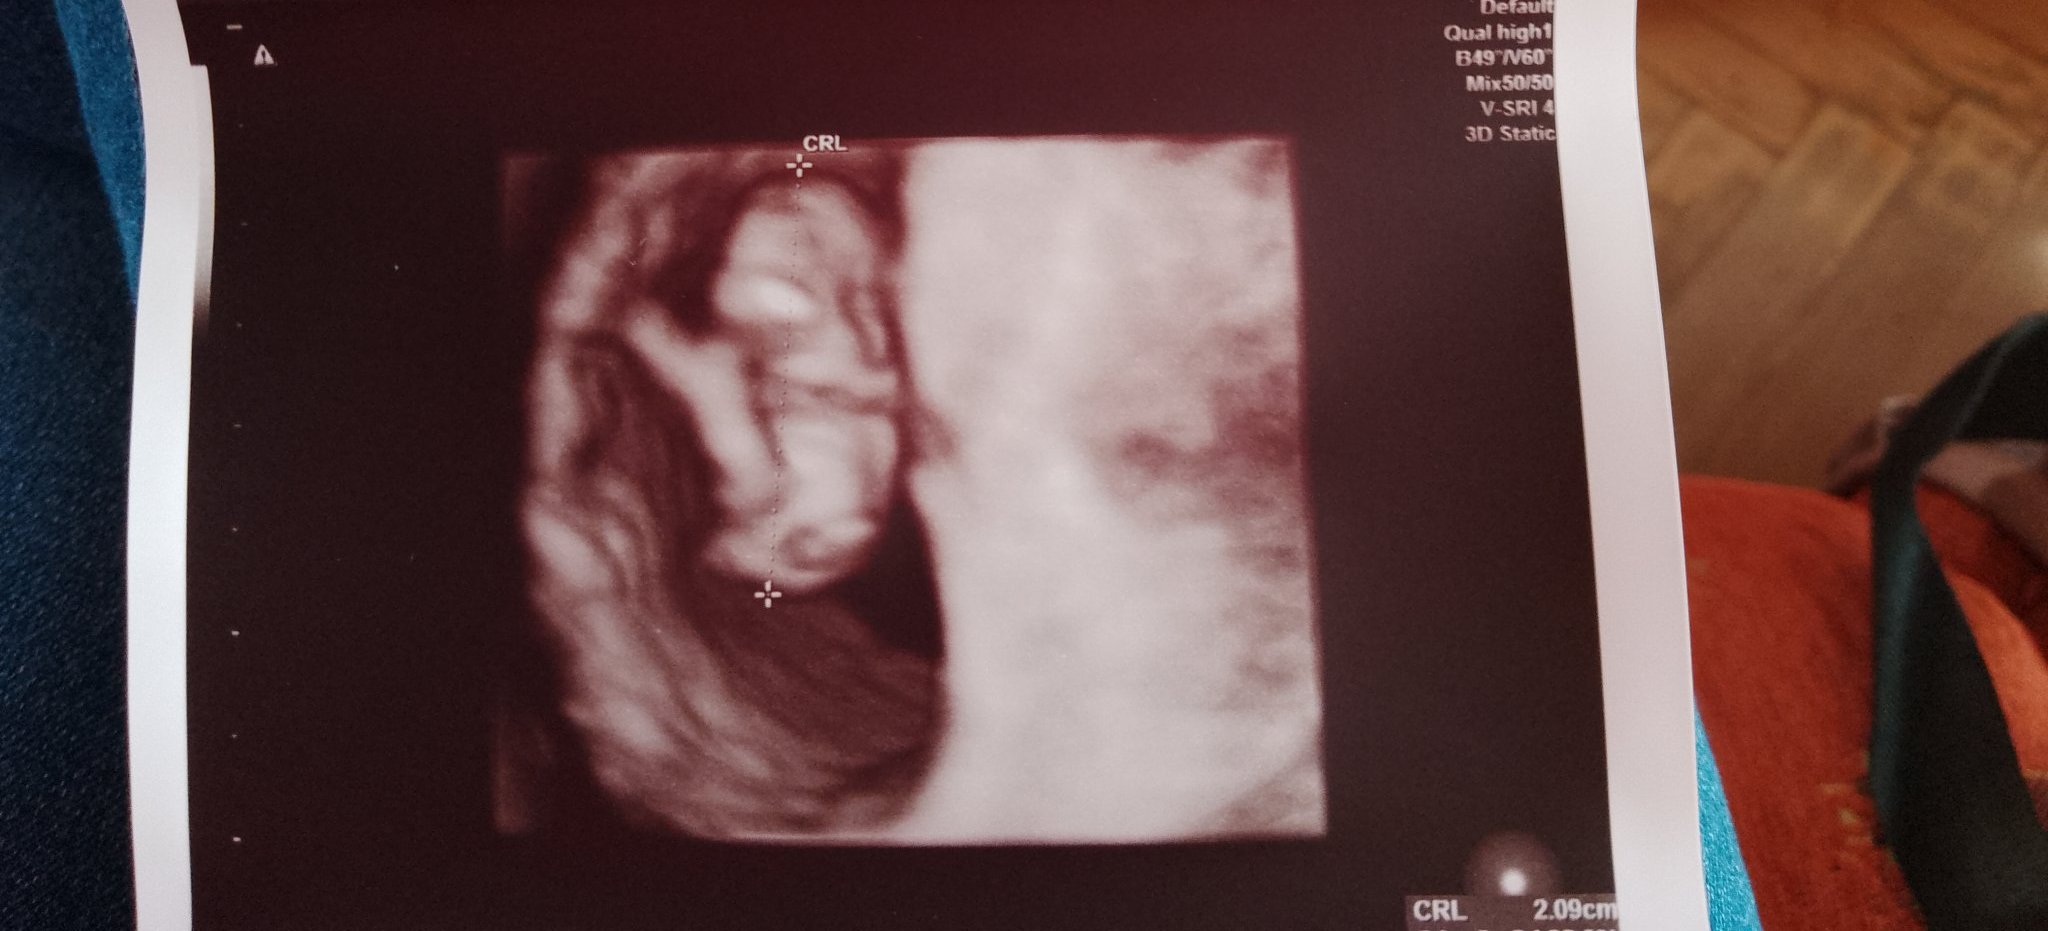

Това е снимка на малкия човек от днес. Бременността ми е на 8 седмици и 4 дена, термин 25 август.